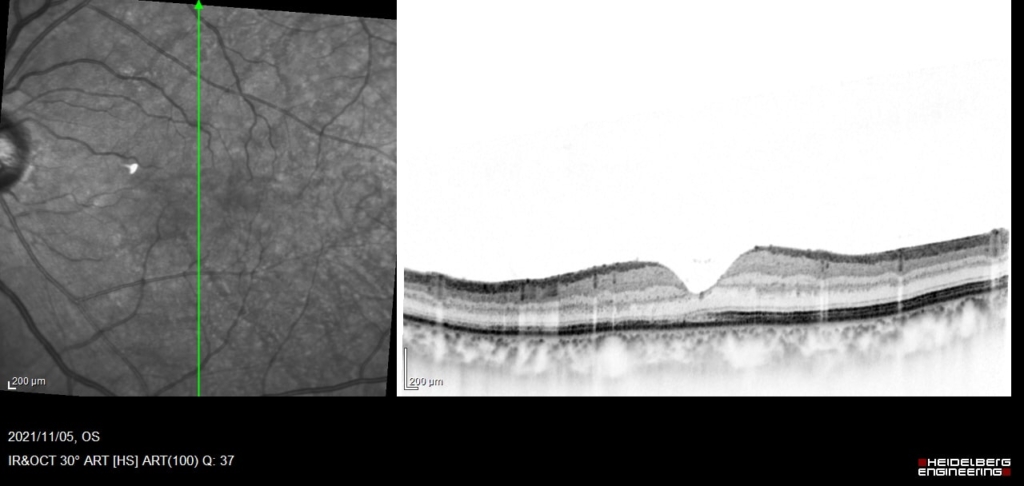

中心窩を含んで網膜剥離があり、外網状層の浮腫と嚢胞様変化がみられる。

術後1か月